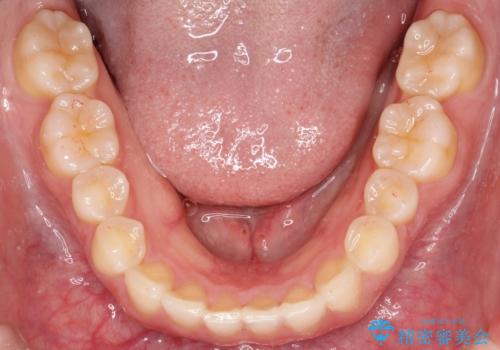

- 前歯のガタガタを綺麗にしたいとのことでインビザラインにて治療を行いました。

治療前は臼歯部反対咬合のため下顎が偏移し正中がずれていましたが、臼歯部反対咬合を改善したことで、正中のズレを改善することができました。